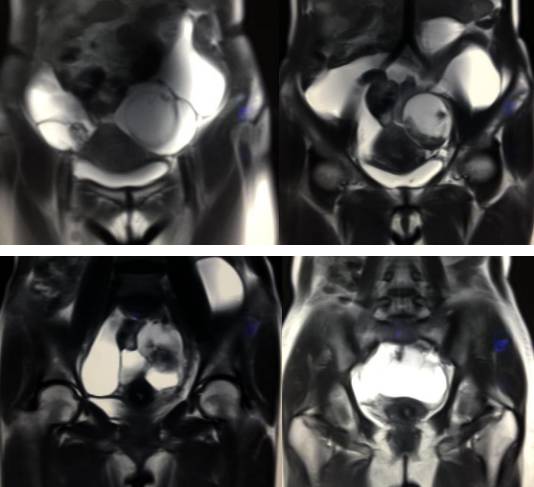

女性,42岁。

主诉:下腹部胀痛不适1月余

病史:自诉13岁时患“结核”,8年前行“左侧附件包块”切除术。

病理结果:黄体血肿

黄体血肿早期:囊内出血较多时,表现为卵巢内近圆形囊肿,囊壁厚,内壁粗糙。

黄体血肿中期:黄体血肿内血液凝固,部分吸收,囊壁变薄而,内壁光滑。

黄体血肿晚期:血液吸收后囊肿变小,转变为白体,内部回声呈实性稍高回

声,与周围卵巢组织分界不清,面靠彩超显示其周围环状血流判断,当血液完全吸收后形成黄体囊肿,囊壁变得光滑,与卵巢其他囊肿难以区分。

根据时间不同MR信号也有所不同,TIWI脂肪抑制序列可以鉴别脂肪和出血。